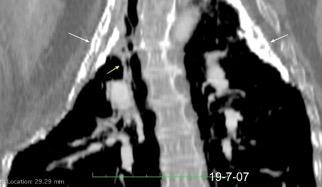

Tb con paquipleuritis calcificada, Hidroneumotórax. Cavidad apical conectada a pleura. Atelectasia redonda

Paquipleuritis calcificada bilateral. En en lado derecho toracoplastia extensa con muñón residual pulmonar con bronquiectasias.